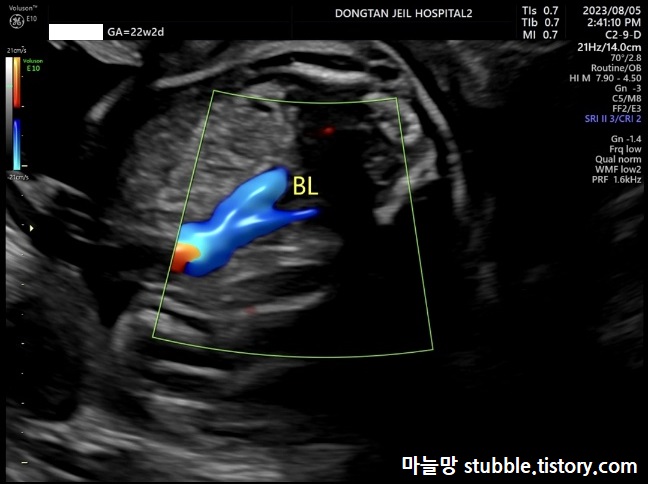

21. 방광(BL)에 오줌이 잘 차고 빠지는지 (태아의 방광은 20분 정도에 한 번씩 비워지고 채워진대요.)

방광에 오줌이 차있는 모습입니다.